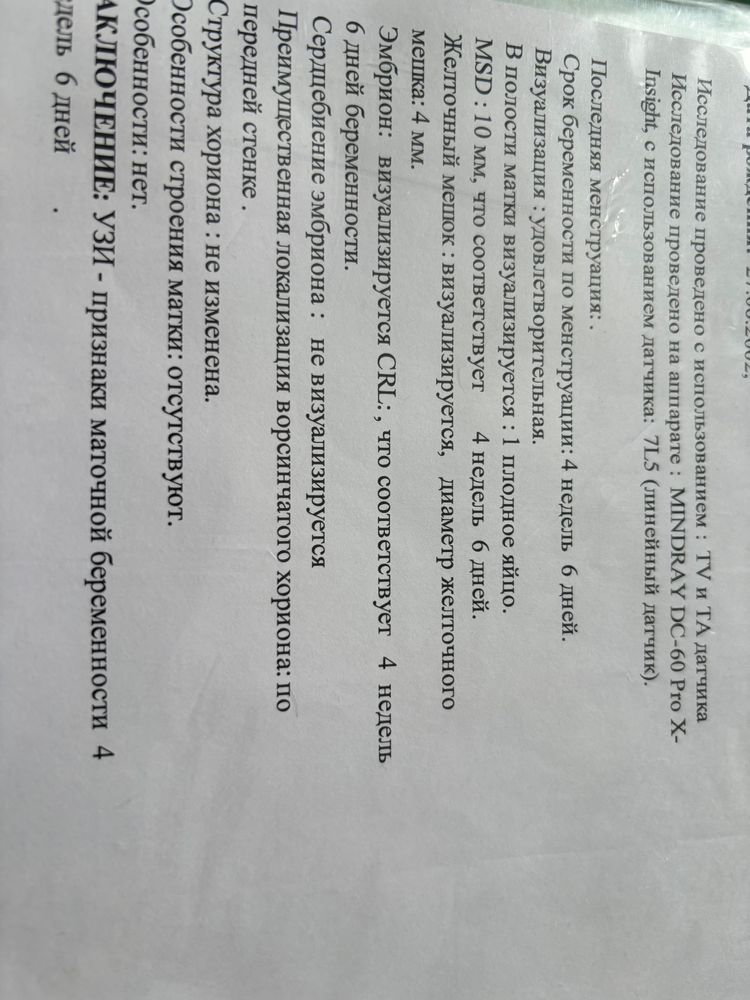

Неделю назад была на узи,подтвердили маточную беременность и на фото как будто бы даже видно эмбрион беременность 4 нед 6 дней. Сердцебиение не прослушивалось,сказали через пару недель подойти. Спустя неделю я пошла на узи в другую клинику,поставили диагноз анембриония,пя растет а эмбрион не визуализируется. Отправили в жк на чистку. Переживаю что может еще рано, по последнему узи беременность 6нед 2 дня

Ничего непонятно и сроки странные пя 10 мм и жм 4 и срок 4,6 недели почему-то хотя размер пя и наличие жм соответствует 5,5 акушерским,плюс непонятно куда делся тогда жм на втором УЗИ,если на первом он был, переделайте УЗИ в этом же месте где первый раз делали

Марина, ну по второму узи спустя неделю срок 6нед 2 дня(расхождение с первым в три дня)

Ничего не понимаю, на первом узи в 4,6н у вас же написано и ЖМ и эмбрион визуализируется. Притом всё соответствует сроку. Сходите на узи в ту же клинику, где были сначала